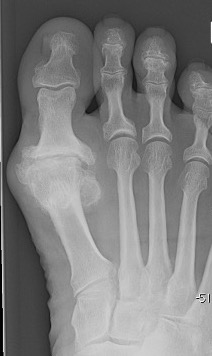

X-ray

Osteoarthritis

- joint space narrowing

- dorsomedial osteophyte

Severe OA